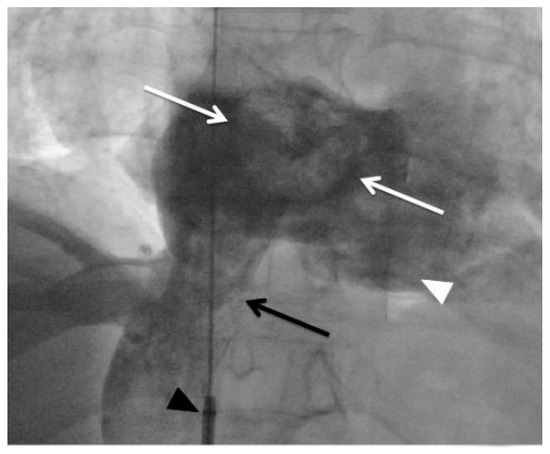

The percutaneous AngioJet™ rheolytic thrombectomy was rapidly and successfully performed at the pulmonary level (Figure 3), and the procedure was interrupted immediately when the haemodynamic condition of the patient had improved with elevation of systemic pressure permitting a diminishing dose of vasopressors. Due to the estimated high risk of dislodgement or fragmentation with subsequent systemic embolisation, the thrombus at the level of the PFO was not approached. The patient left the cardiac catheterisation laboratory under full heparin anticoagulation with stable haemodynamic conditions. Over a few hours, a progressive weaning from the vasopressor was possible and a second TEE performed 12 h following the procedure confirmed the improvement of the right ventricular function in the absence of residual intra-atrial thrombus. Without any further neurologic deterioration, the patient could be extubated on day 7 and she could be discharged from the hospital on day 60 with only mild neurological sequelae. At 12 months, she was still doing well without relapse on oral anticoagulation.

Figure 3. Pre-thrombectomy pulmonary angiogram (AP view): (A)Extensive thrombus occluding the right superior and middle lobar arteries (white arrow) and severely impairing flow in the inferior lobar artery (black arrow). After AngioJet™ Rheolytic Thrombectomy pulmonary angiogram (AP view): (B) Selective injection showing a near normal perfusion in the right superior and middle arteries (white arrow). (C)Selective injection showing an improved perfusion in the inferior lobar artery (black arrow). * Trans-oesophageal echocardiography probe.